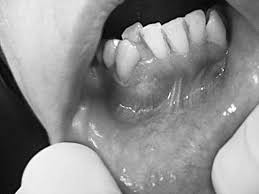

این کیست بیشتر در اطراف دندانهای نیش بالا و عقل پایین و در اطراف تاج دندان ایجاد میشود. علت به وجود آمدن کیست دنتیجروس، فشاری است که بر روی فولیکول وارد میشود. این فشار وارده باعث ایجاد اختلال در جریان خون و تجمع مایع میان بافت غشای مینای دندان میشود. کیست فولیکولار به سرعت رشد میکند به همین دلیل به محض مشاهده باید به متخصص مراجعه شود.

در درمان کیست دنتیجروس و یا فولیکولار ناحیه آسیب دیده را برداشته و کیست را جراحی میکنند در بیشتر مواقع این نوع درمان موفقیت آمیز است.